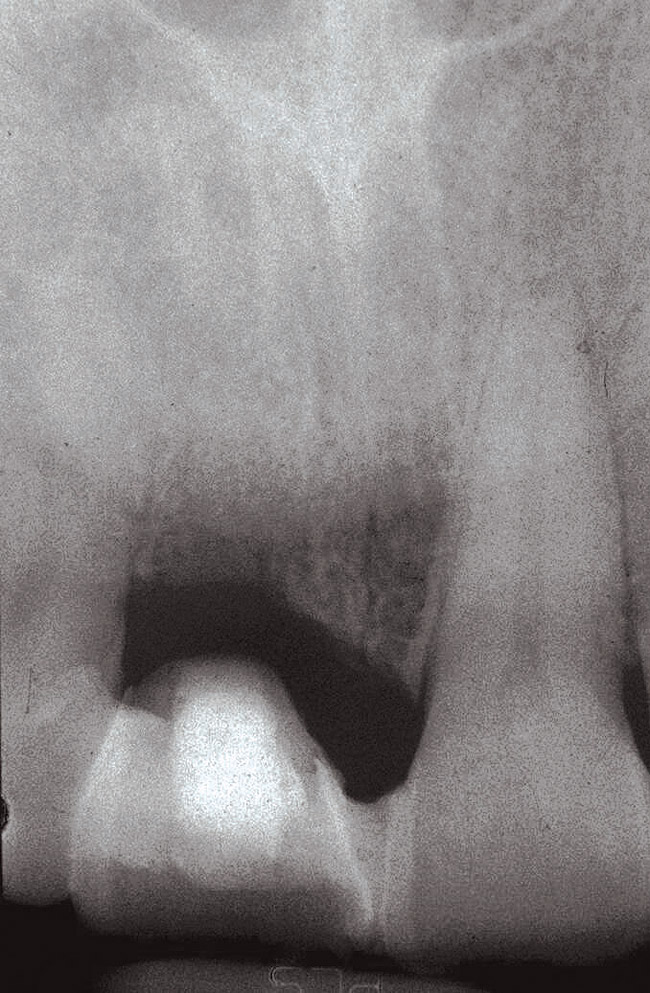

Fig 2. After implant placement, the radiograph suggests that without the planned surgical crown lengthening on the adjacent teeth, the implant crown would emerge substantially more apically than the adjacent natural teeth.

Figure 2